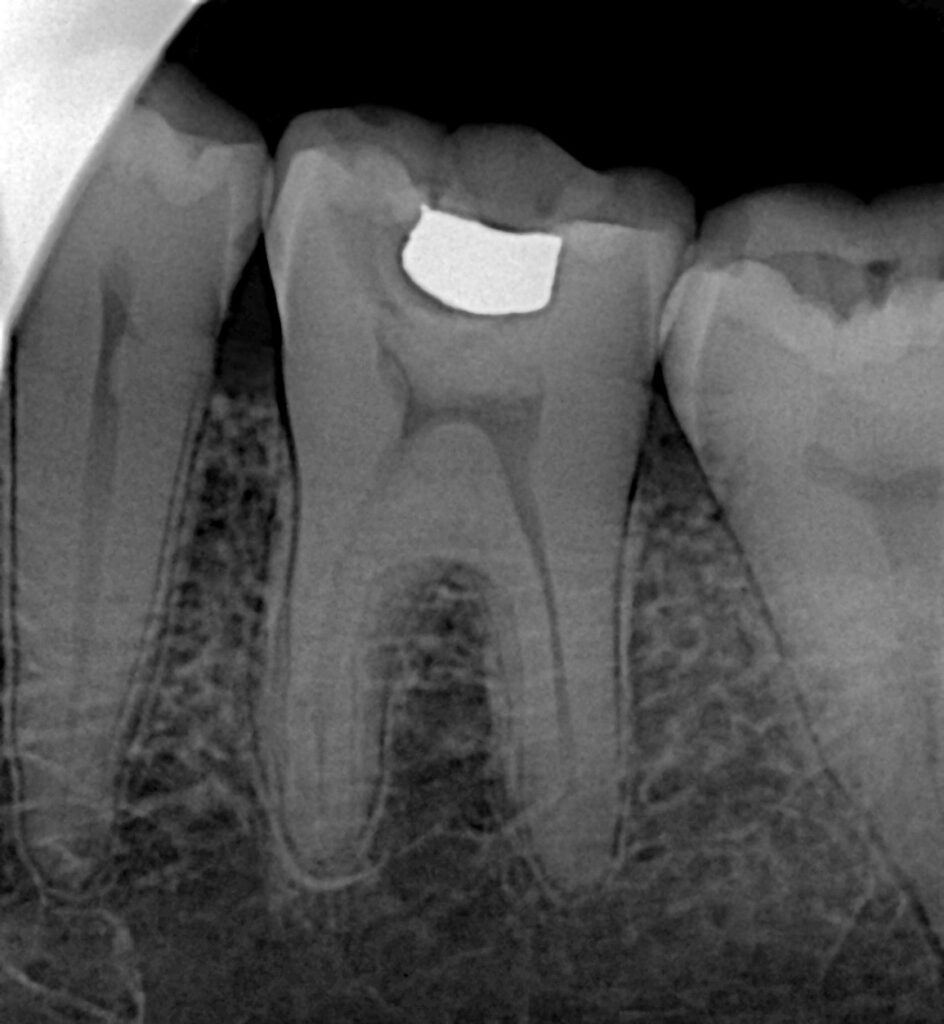

A mandibular first molar (lower 6) presented with deep carious involvement and symptoms consistent with irreversible pulpitis. Radiographic assessment revealed intact periapical structures with no evidence of apical pathology. Given the favorable biological status, a single-visit endodontic and restorative approach was planned.

All canals were identified and negotiated under magnification. Cleaning and shaping were performed using a crown-down approach with copious irrigation to ensure effective disinfection while minimizing dentin removal. Canals were obturated in the same visit following confirmation of working length and apical patency.

The final restoration provided immediate cuspal protection, an effective coronal seal, and restoration of occlusal function. Radiographic evaluation confirmed dense root canal obturation and proper adaptation of the restorative material.